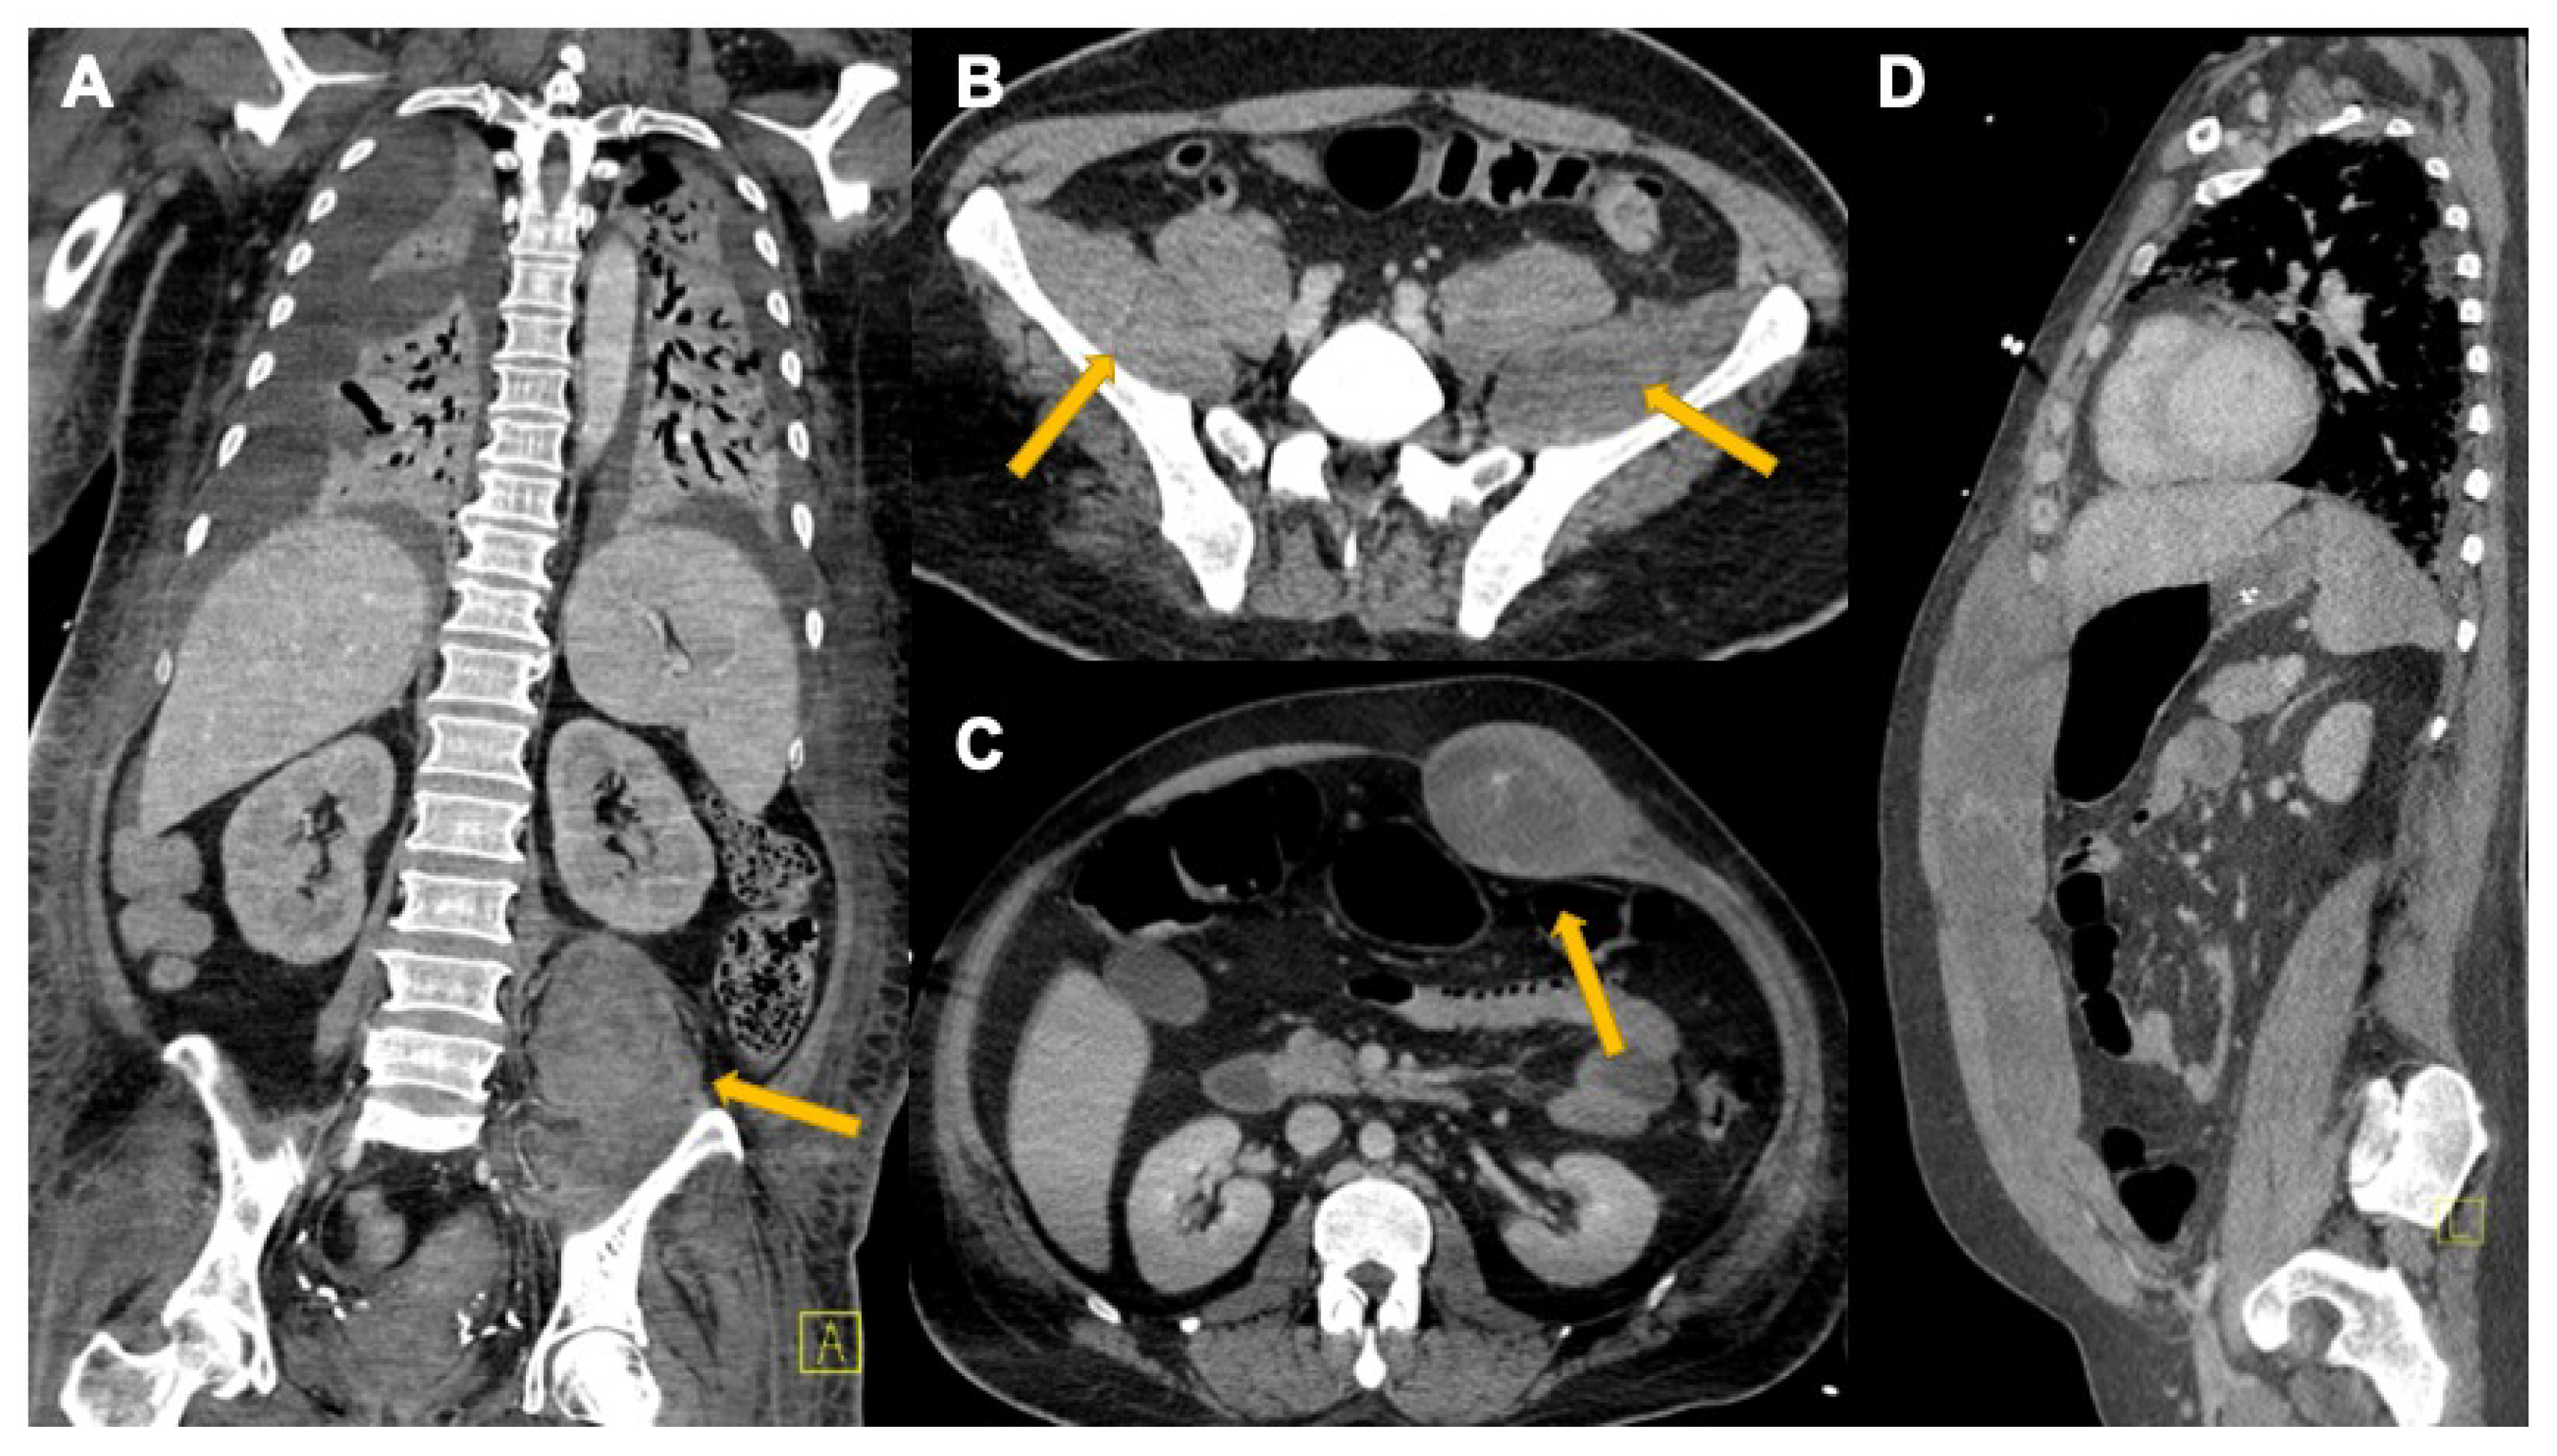

3.3. Abdominal Manifestations